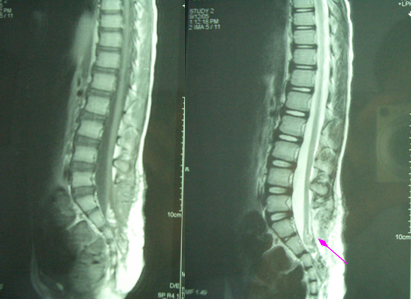

术后影像学资料显示:完整的、椎管内水平的硬膜结构。